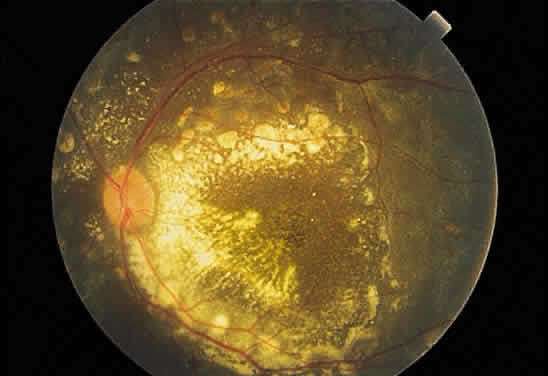

Fibrous tissue may originate from the choroid and proliferate through breaks

in Bruch's membrane into the subpigment epithelial or subretinal

spaces,4 hence the white appearance of disciform macular degeneration (Fig. 16). Fibrous tissue also may originate from fibroblasts located in the adventitia

of retinal vessels and may contribute to the white appearance

of vascularized membranes (Fig. 17A), such as those seen in proliferative diabetic retinopathy (see Fig. 17B) or arterioles after vascular occlusion (see Fig. 6). The accretion of collagen in the wall of the vessel in arteriolosclerosis

may thicken the vessel wall (see Fig. 5) and alter the color of the blood column to a copper or silver color. Injury

to the pigment epithelium results in scar formation (Fig. 18). Collagen deposition from pigment epithelium metaplasia may be identified

by the presence of pigment within a scar (Fig. 19). Injured nonpigmented epithelium may undergo similar fibrous metaplasia

and may contribute to the formation of membranes such as cyclitic membranes

in the region of the ciliary body.  Fig. 16. Fundus photograph of a disciform macular scar, white because of fibrosis

and atrophy of the pigment epithelium. A broad, C-shaped, fresh hemorrhage

within the sensory retina surrounds it. Fig. 16. Fundus photograph of a disciform macular scar, white because of fibrosis

and atrophy of the pigment epithelium. A broad, C-shaped, fresh hemorrhage

within the sensory retina surrounds it.